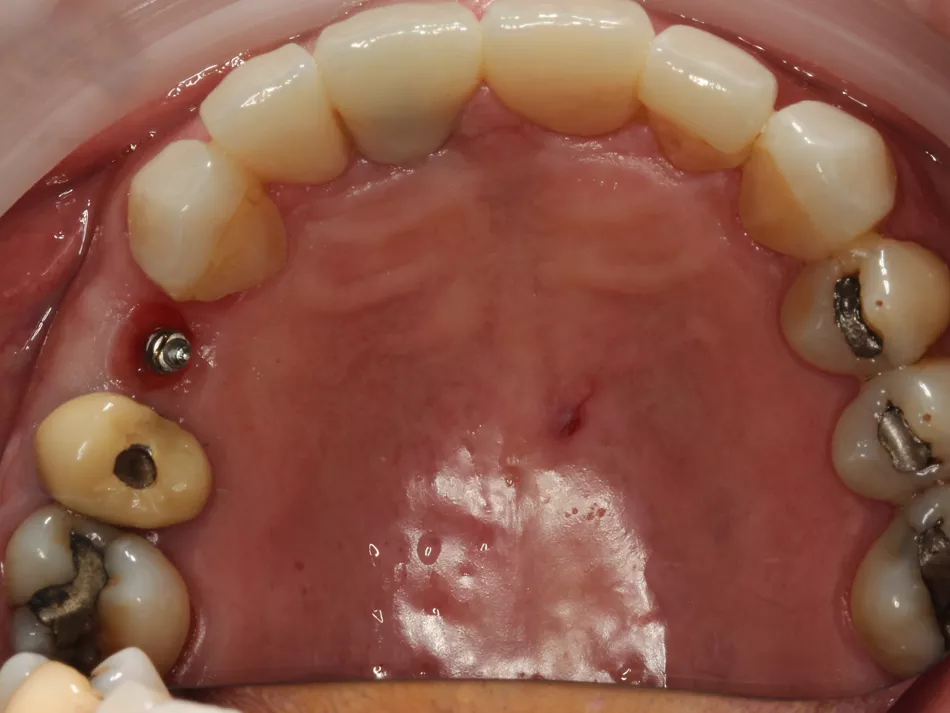

Soft‑tissue healing differed notably between the two sites. The mesial implant restored with a HealFit® SH abutment showed thicker, well‑adapted peri‑implant mucosa with minimal erythema inflammation and a stable, guided emergence profile, reducing the need for secondary tissue conditioning. In contrast, the distal implant with a traditional healing abutment demonstrated localized redness, a compressed circular healing pattern, and no guidance of soft‑tissue contour, features commonly associated with conventional implant exposure techniques, which can produce increased soft‑tissue reactivity and later need for tissue shaping.

12a. 12b. 12c. 12d. 12e. Soft‑tissue healing comparison: HealFit® SH shows anatomic, well‑shaped mucosa, while the conventional healing screw displays a flat, compressed circular pattern.

12a

12b

12c

12d